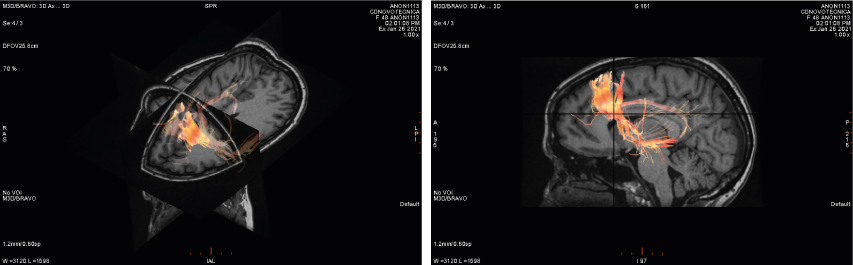

- Tractografía

TENSOR DE DIFUSIÓN

Mediante unos mapas de colores la difusión permite realizar una tractografía permitiendo valorar especialmente los tractos de sustancia blanca a nivel cerebral y realizar un mapa de la red de fibras nerviosas. Entre sus aplicaciones fundamentalmente permite valorar isquemia cerebral, enfermedades desmielinizantes, epilepsia, patología tumoral y se está empezando a estudiar en demencias y trastornos neurodegenerativos.